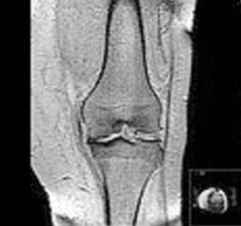

Osteoarthritis (OA)

The word Osteoarthritis is derived from Greek language. Osteo meaning “of the bone”, arthr meaning  “joint” and itis meaning “inflammation”. Thus Osteoarthritis means ‘inflammation of joints’. Osteoarthritis (OA) also known as degenerative arthritis, degenerative joint disease(DJD), or osteoarthrosis, is a type of joint disease that results from breakdown of joint cartilage and underlying bone.The most common symptoms are joint pain and stiffness. Initially, symptoms may occur only following exercise, but over time may become constant. Other symptoms may include joint swelling, decreased range of motion, and weakness or numbness of the arms and legs in cases where the back (backbone-spinal column) has been affected. The most commonly involved joints are those near the ends of the fingers, at the base of the thumb, neck, lower back, knees, and hips. Joints on one side of the body are often more affected than those on the other. Usually the problem crops up gradually over the years with increase in the age of a person. It can affect work as well as normal routine activities in life particularly the ones involving fine motor skills. Unlike other types of arthritis, only the joints are typically affected in Osteoarthritis.

Osteoarthritis is the most common form of arthritis associated with disease of the knee and hip.